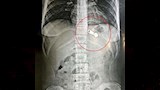

كان مستشفى دسوق العام استقبل طفلة تبلغ من العمر 12 عامًا، تعاني من آلام حادة ومستمرة في البطن، ووفق ذلك أجريت الفحوصات والأشعة الطبية اللازمة فيما أظهرت الفحوصات وجود جسم غريب (سوستة معدنية كبيرة الحجم) مستقرة في وضعية دقيقة داخل المعدة.

وتبين من خلال الفحص أن الجسم الغريب ظل ملتصقًا بالغشاء المخاطي للجزء العلوي من المعدة لمدة أسبوع كامل، ما زاد من صعوبة الحالة وخطورة حدوث تقرحات أو ثقب في جدار المعدة.